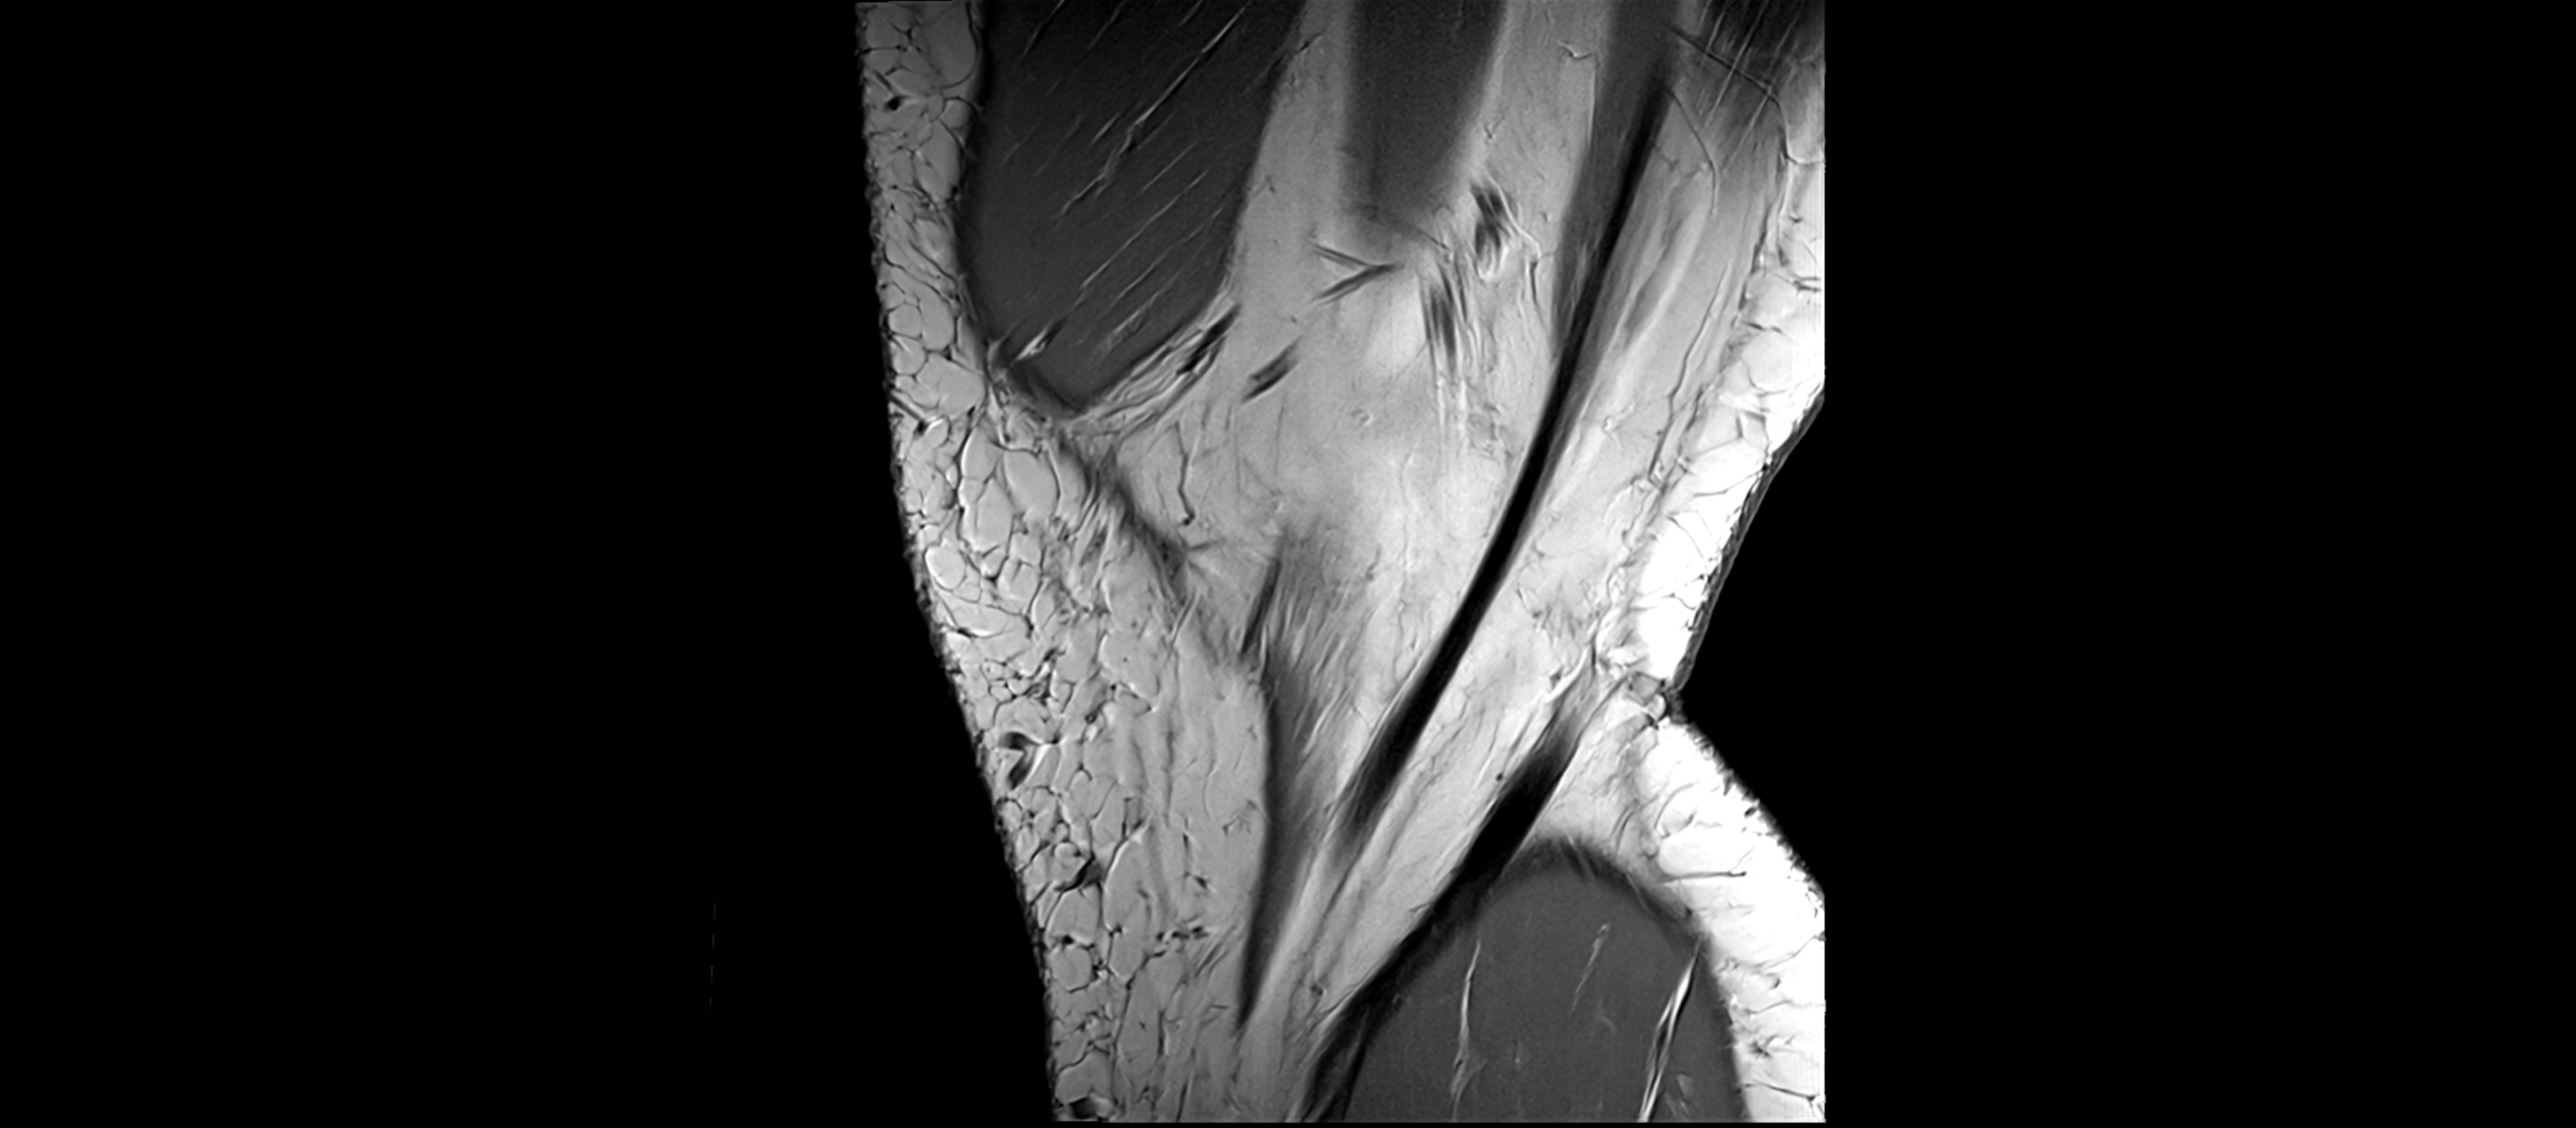

MRI images

image

MRI Appearance

T2-weighted images:

• Normal ACL remains low signal

• Partial or complete tears appear as discontinuity, increased signal, or fiber laxity